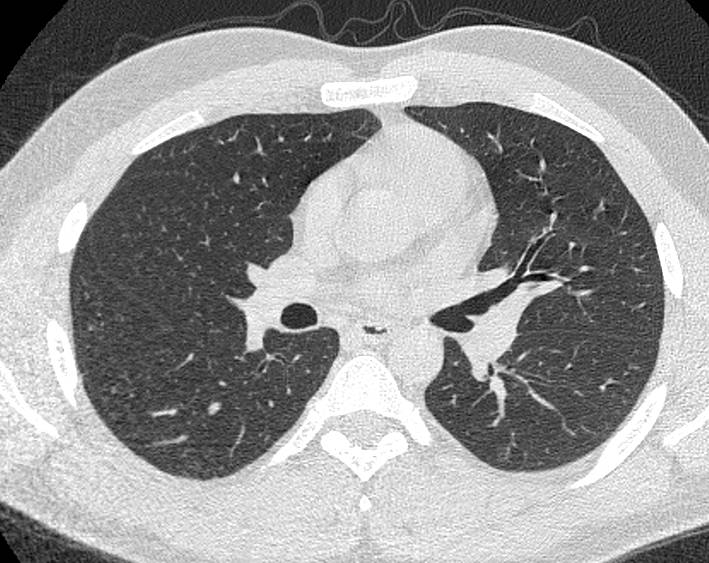

В нашей клинике КТ бронхов проводится на новейшем 128-срезовом мультиспиральном компьютерном томографе экспертного класса TOSHIBA AQUILION CXL. Аппарат оснащен увеличенным количеством сверхчувствительных детекторов, которые позволяют проводить тончайшие срезы анатомической области с толщиной от 0,5 мм за несколько секунд. Быстрое выполнение процедуры обеспечивает минимальный уровень рентгеновского облучения, при этом исследование выполняется без применения контрастирования.

На основе данных, полученных при сканировании, аппарат создает наглядную 3D модель бронхиального дерева с высочайшей точностью и достоверностью, которая позволяет просматривать интересующие анатомические структуры в разных плоскостях. Метод обладает высокой точностью и дает возможность исследовать мелкие бронхи и бронхиолы, которые из-за узкого просвета бывает невозможно осмотреть при помощи эндоскопической бронхоскопии (возможности метода ограничены размером зонда).

С помощью виртуальной бронхоскопии можно выявить объемные образования в трахее, бронхах, определить степень сужения просвета дыхательных путей. Кроме того, компьютерная томография позволяет оценить состояние окружающих тканей, выявить прорастание опухоли в близлежащие органы, обнаружить метастазирование в регионарные лимфоузлы и ткань легкого.